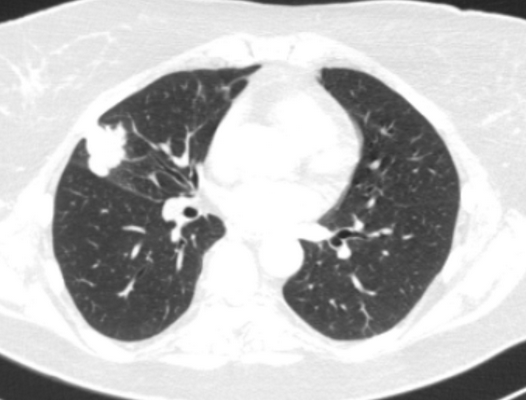

(а) Пациент, перенесший левостороннюю верхнедолевую лобэктомию. При рентгенографии органов грудной клетки в /7/7 проекции определяются объемное уменьшение левого легкого, высокое расположение корня левого легкого и смещение влево верхних отделов средостения.

(б) У этого же пациента на совмещенных изображениях при КТ с контрастным усилением визуализируются смещение влево переднего средостения и хирургические скобы в культе верхнедолевого бронха.. При левосторонней лобэктомии междолевая щель не формируется.